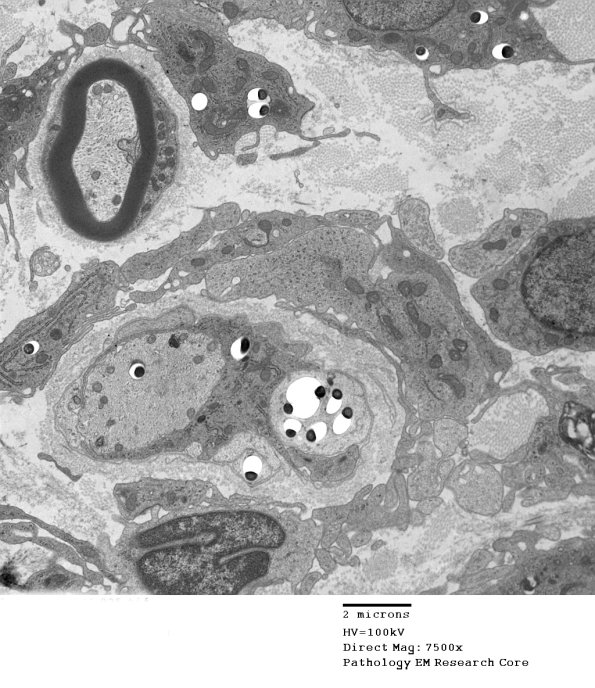

1D4A,B In this case the Schwann cell contains organisms adjacent to and within the demyelinated axon. (electron micrograph)